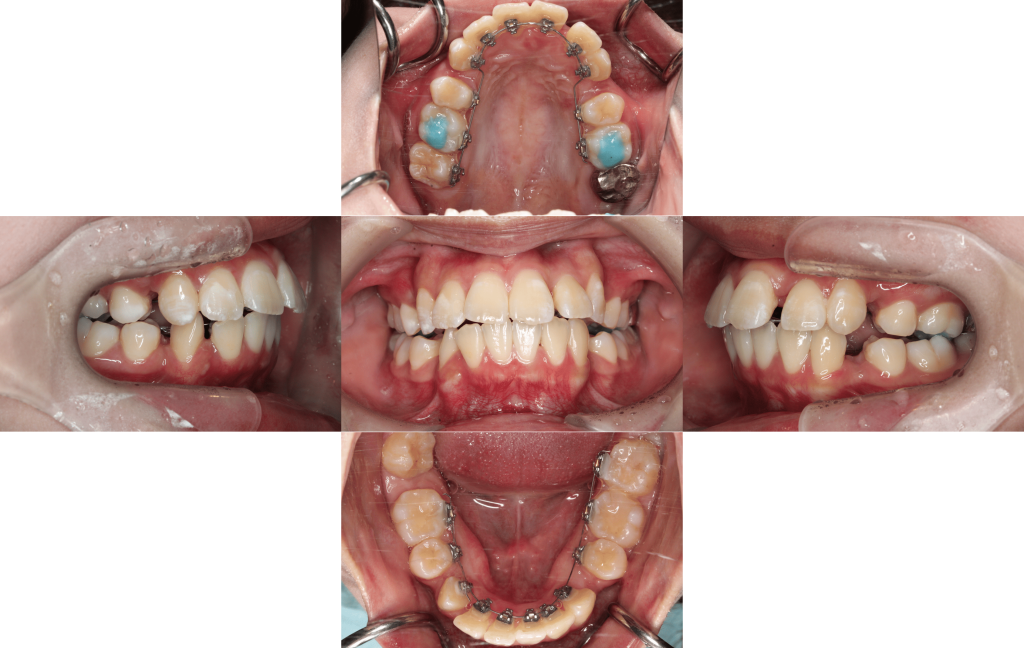

After

約1年後

約1年6か月後